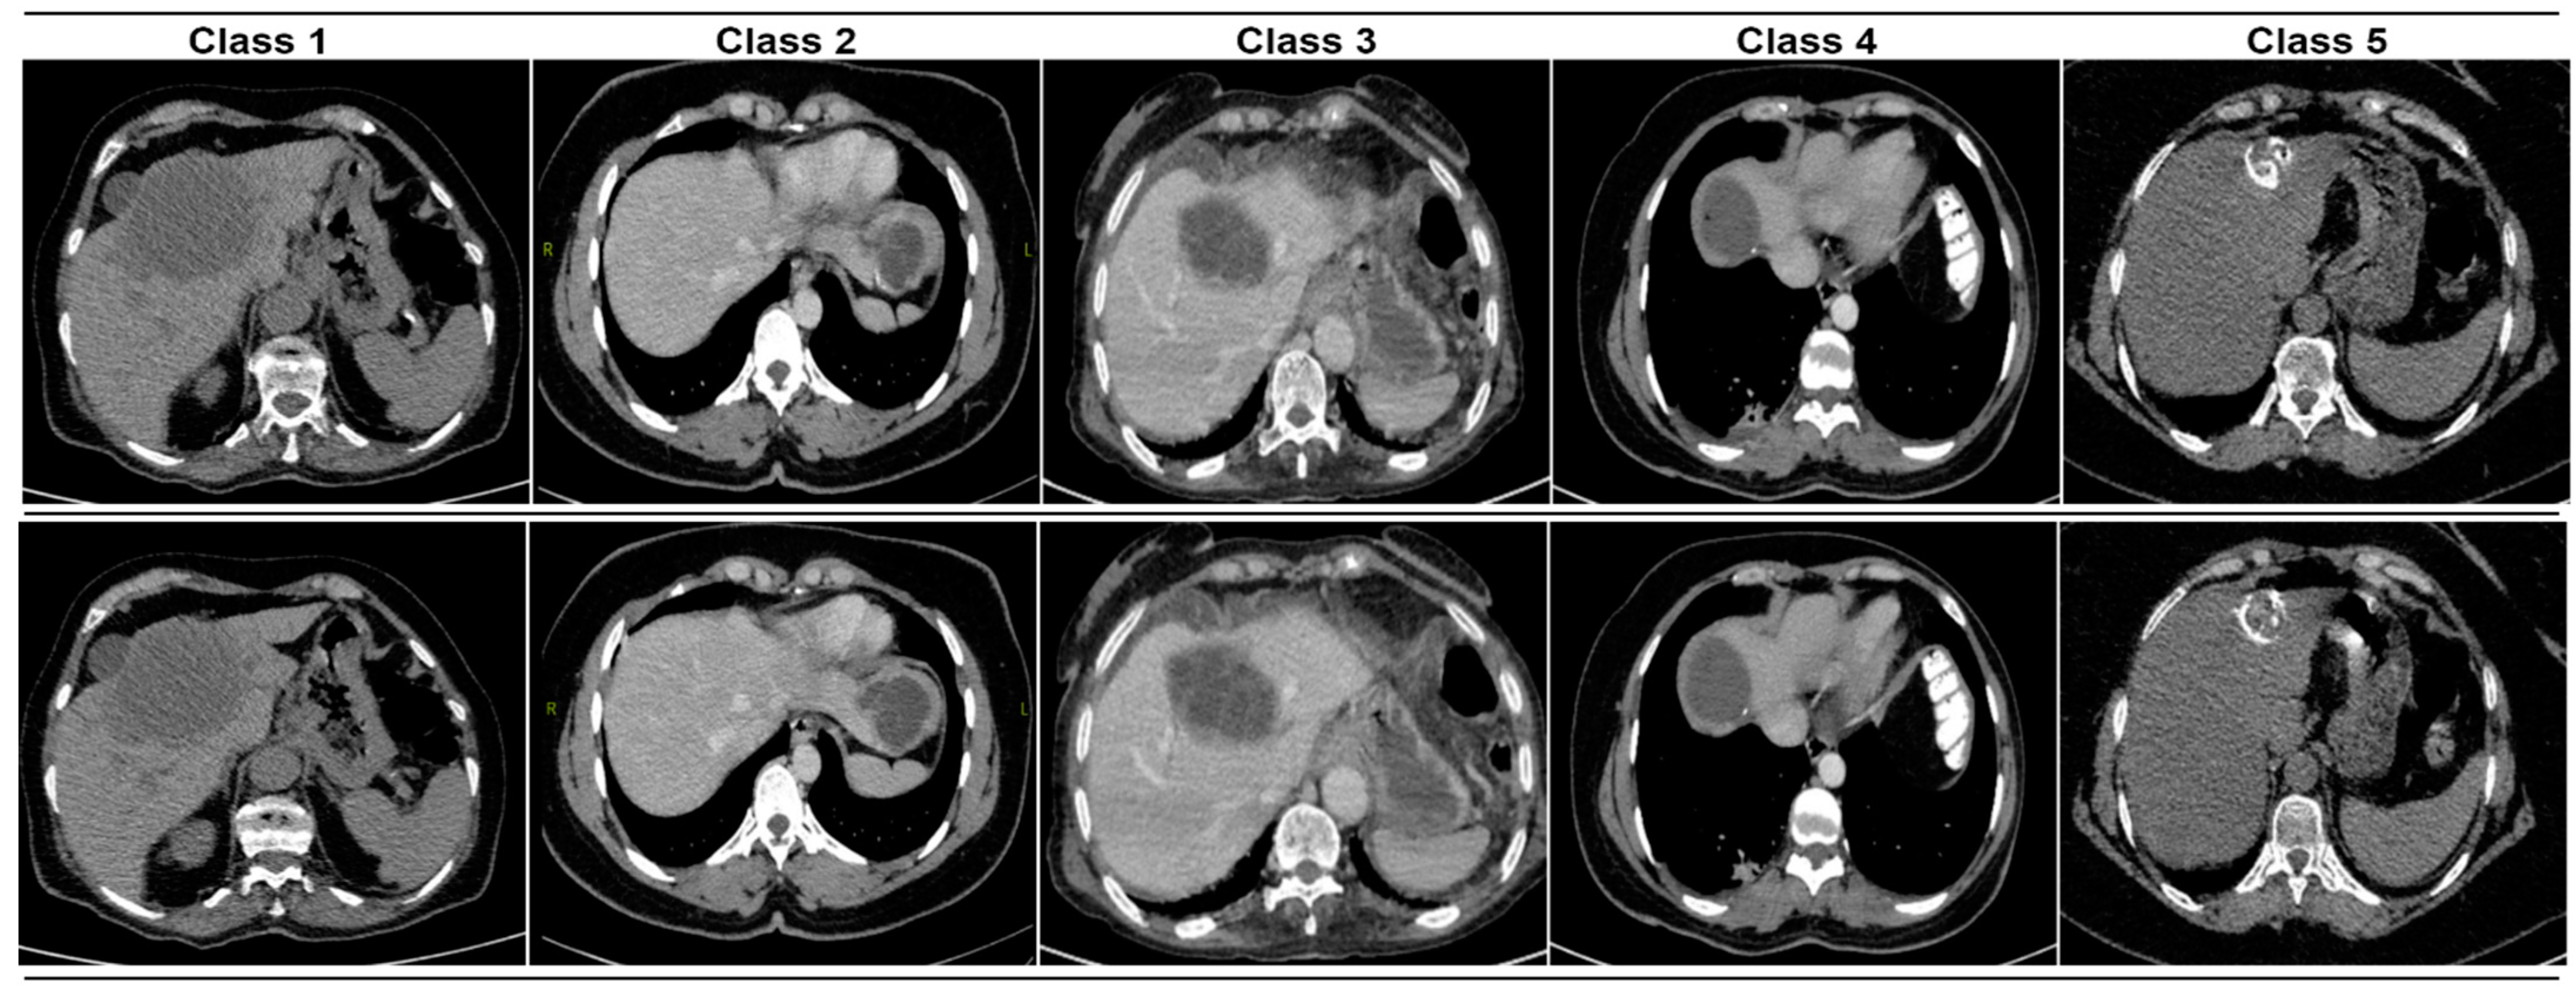

Hydatid cyst treatment can be performed with methods such as antiparasitic drugs or surgical intervention. The dataset used in this paper was downloaded from the Kaggle platform [,]. This dataset consists of 5 classes. Image examples for each class in the dataset are provided in Figure 1.

Figure 1.

Hydatid cyst CT images.

There are 251 CT images in the 1st class, 541 in the 2nd class, 444 in the 3rd class, 442 in the 4th class, and 738 in the 5th class.